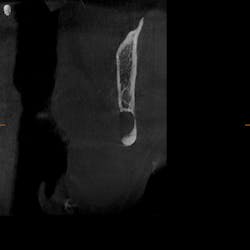

As part of our intake process to make a sleep mandibular advancement device, we take a cone beam image (figures 1–4). This way we can evaluate sinuses, septum, turbinates, teeth, and jaws.

Upon examination, it was noted that a dark, radiolucent lesion was present on the lower right jaw, anterior to the angle of the mandible. The patient didn’t have any pain, symptoms, or knowledge of the lesion. It was not palpable. He reported that he had his third molars removed in his twenties with no complications.

The Stafne defect is code for a depression in the bone, a concavity, due to the submandibular gland. In addition, it can’t be qualified as a cyst because there is no epithelial lining or fluid content. It does usually occur more in men as well.1 There is no treatment necessary; it’s something we can just monitor.